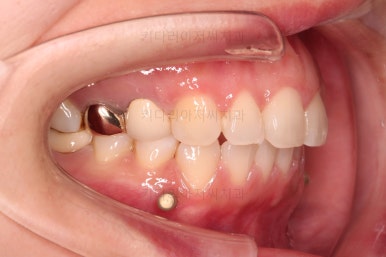

어금니의 맞물린은 100점은 아니지만 생활하기에 크게 나빠보이지 않고요.

특히 임플란트도 있는 상황이었기 때문에 굳이 어금니까지 교정할 필요는 없어보였어요.

앞니 부분교정으로 치료계획을 세웠는데 다른 분들에 비해 난이도가 높은 치료가 예상되었던 이유는 우측 상단의 사진에 선 그어놓은 부분을 보시면 어금니에 비해 아래앞니가 약간 솟구쳐 높이가 맞지 않다는 점이었어요.

이 부분을 개선하기 위해 일반적인 부분교정 외에 추가적인 장치가 필요했었습니다.

그리고 아랫니 송고니 옆 잇몸에 보시면 미니스크류가 식립이 되어있는데요.

이는 솟구친 아래 앞니의 높이를 조절하기 위해 사용이 됩니다.

이부분이 해결이 되어야 좀 더 완성도 높은 부분교정이 가능해요.

이번 환자분은 아래 앞니의 높낮이도 맞춰줘야해서 미니스크류까지 이용한 상황이었으나 6개월 정도 걸려서 비교적 발리 마무리 될 수 있었어요.

조금더 디테일을 조절하고 부산부분치아교정 마무리를 합니다.